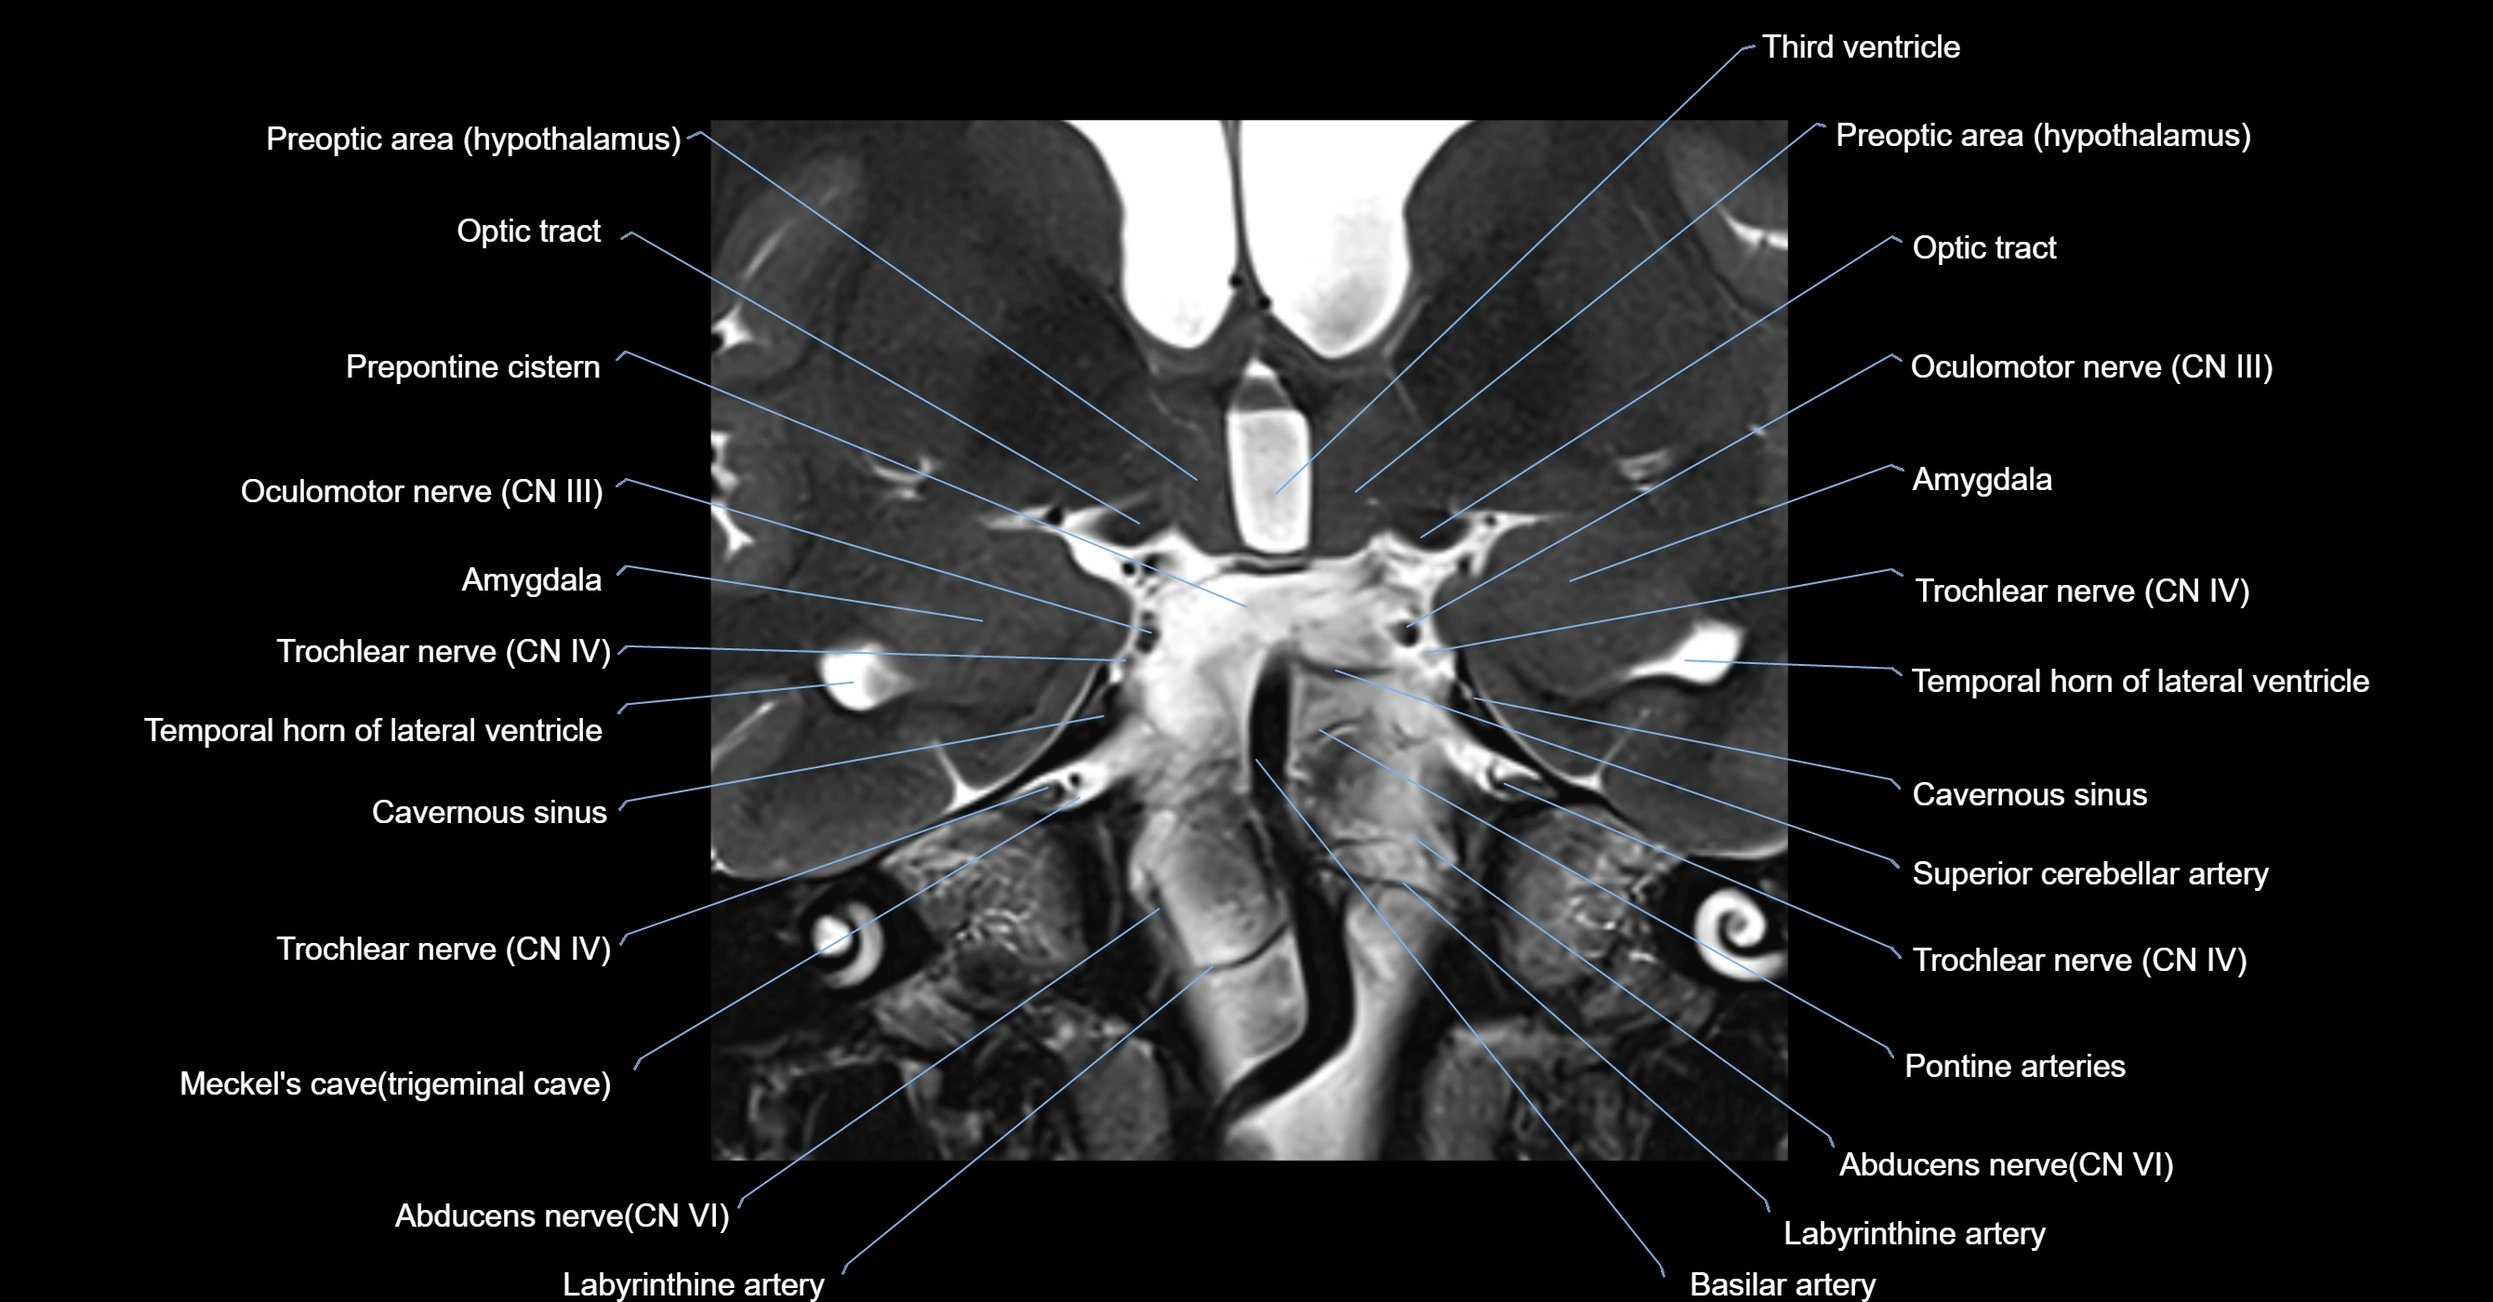

MRI Appearance

The abducens nerve is a small, thin, linear structure

Best visualized on high-resolution T2-weighted 3D MRI sequences (e.g., FIESTA or CISS)

Seen as a hypointense (dark) line running from the brainstem at the pontomedullary junction, traversing the prepontine cistern, and entering Dorello’s canal under the petrosphenoidal ligament, then into the cavernous sinus, and finally the orbit

May be challenging to visualize in standard MRI due to its small size

Pathology may be inferred by absence, displacement, or enhancement of the nerve

MRI images